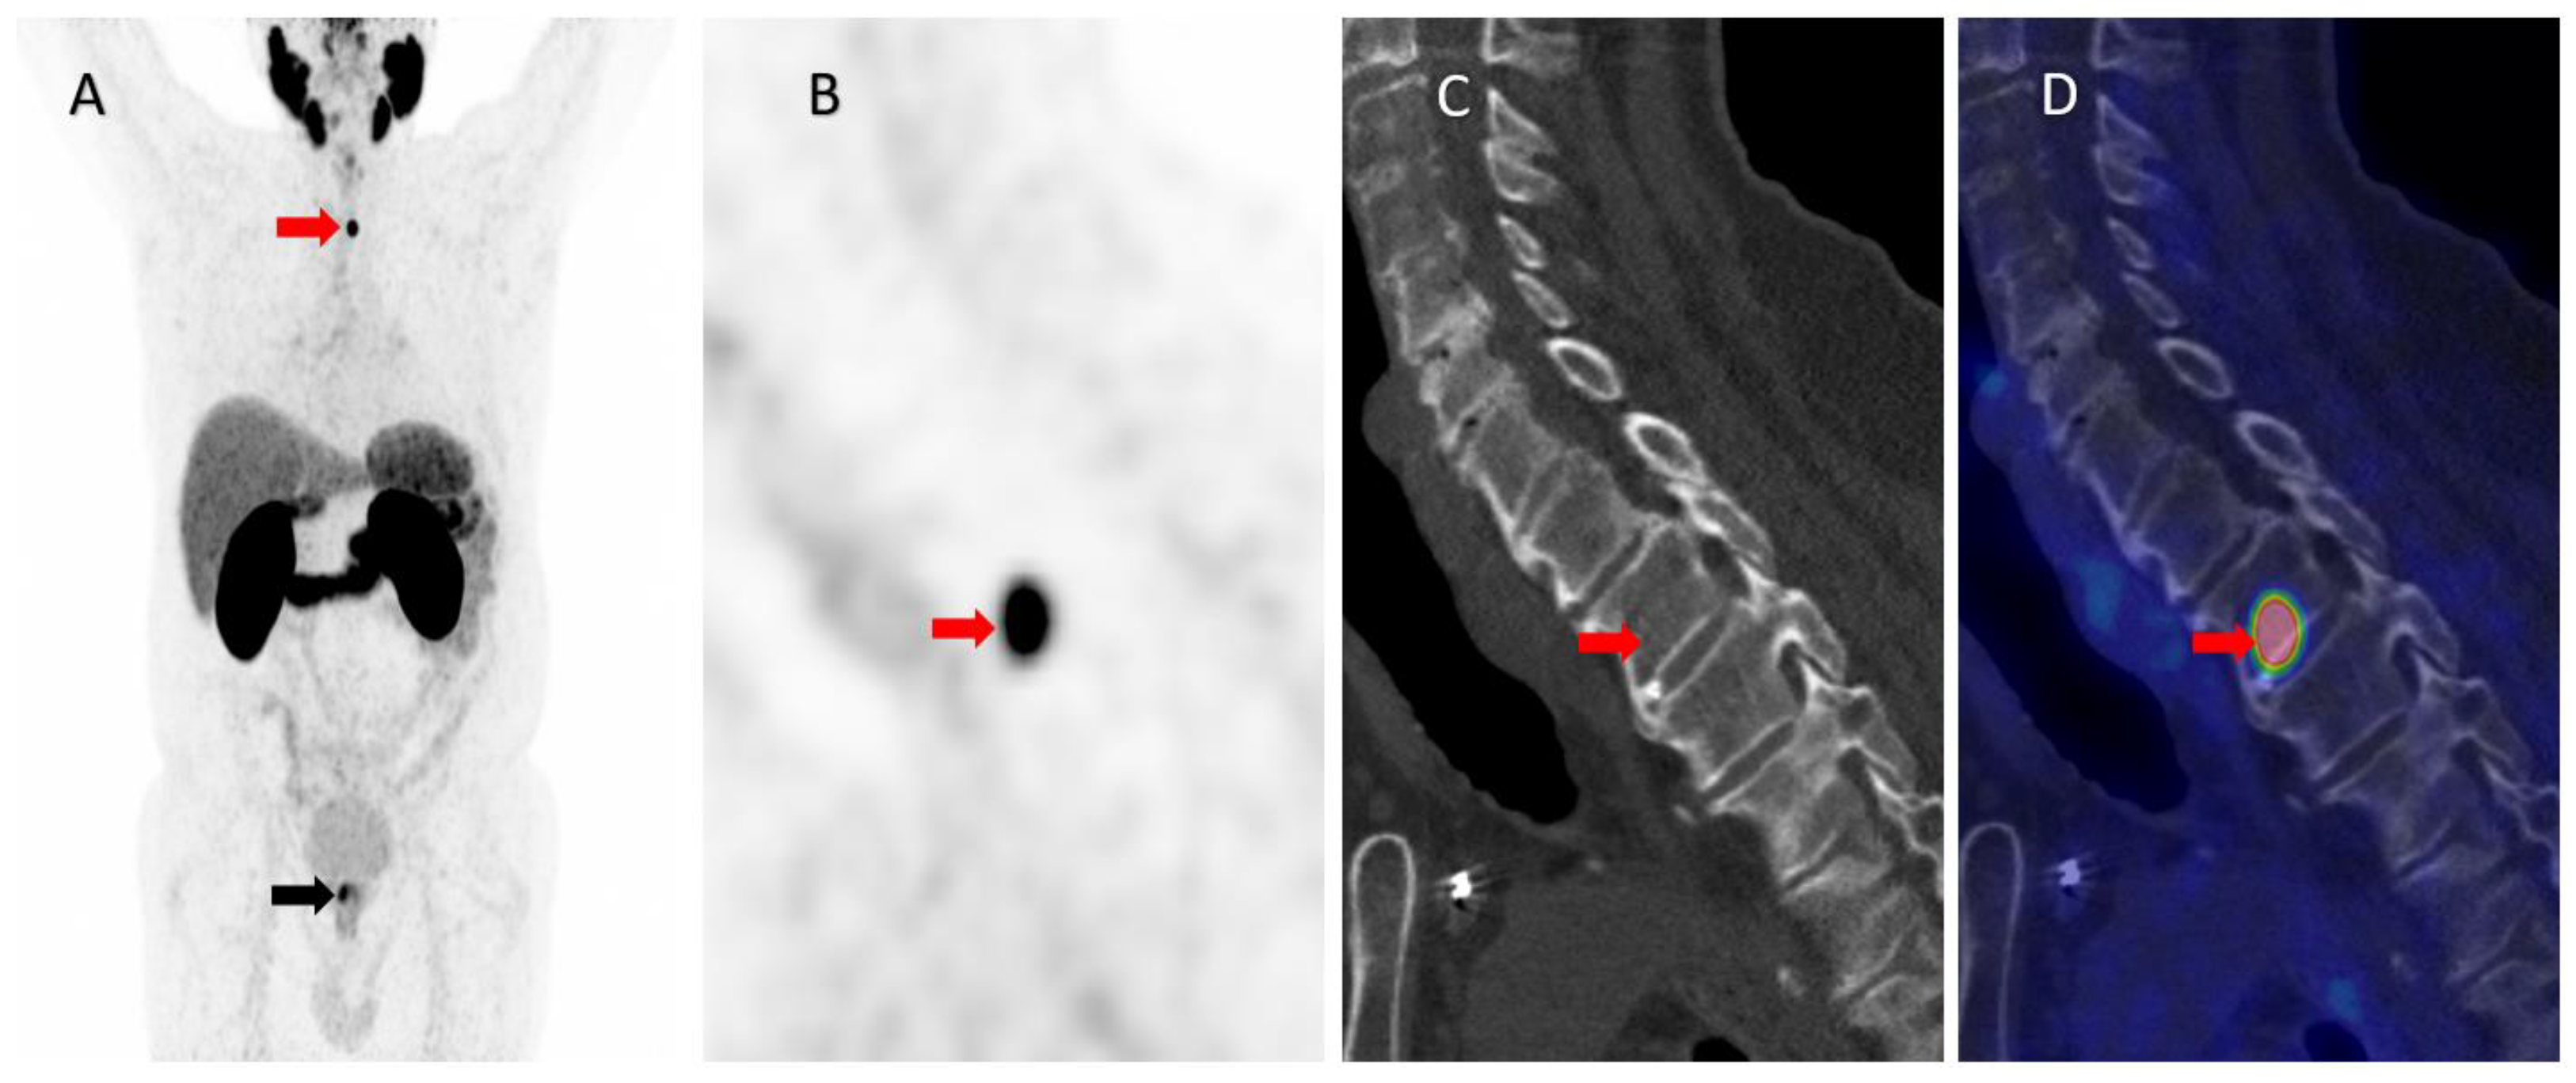

Intense PSMA Uptake in a Vertebral Hemangioma Mimicking a Solitary Bone Metastasis in the Primary Staging of Prostate Cancer via 68Ga-PSMA PET/CT

Gossili, F.; Lyngby, C.G.; Løgager, V.; Zacho, H.D. Intense PSMA Uptake in a Vertebral Hemangioma Mimicking a Solitary Bone Metastasis in the Primary Staging of Prostate Cancer via 68Ga-PSMA PET/CT. Diagnostics 2023, 13, 1730. https://doi.org/10.3390/diagnostics13101730